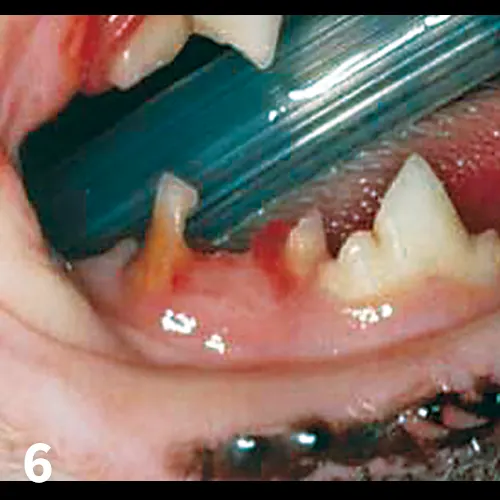

Untreated, the disease may progress to juvenile onset periodontitis, in which plaque and calculus form more rapidly and may result in significant gingival recession, furcation exposure, bone loss, and periodontal pocket formation. (See Figure 2.) Teeth that lose more than 50% support should be extracted.

Side view of cat’s mouth showing perigingival inflammation and grey-to-black accumulations on surfaces of teeth.

FIGURE 2

Feline juvenile periodontitis